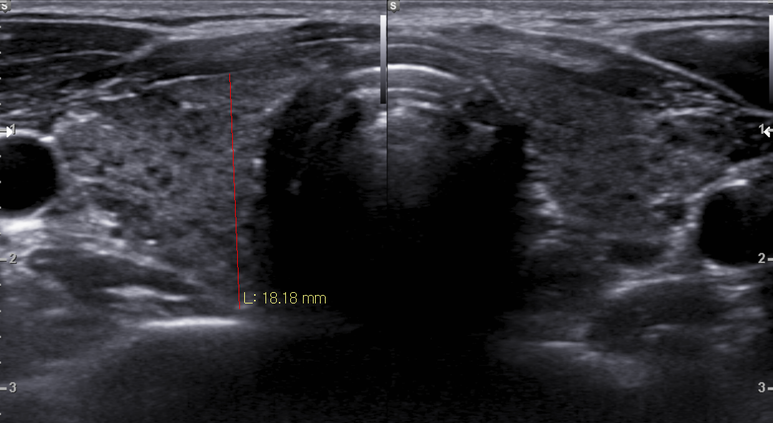

area VI 에 LN로 생각되는 결절

림프절 크기는 약간의 변화

결절의 크기가 증가함

hilum의 혈관이 잘 관찰됨